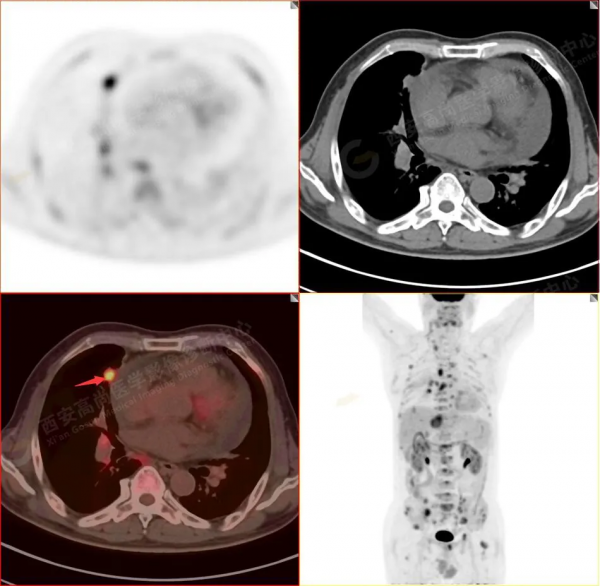

1.以下為肺內原發灶

1.右肺中葉內側段軟組織結節,呈淺分葉狀,邊緣可見毛刺及胸膜牽拉徵,呈FDG代謝異常增高,考慮為周圍型肺癌。

2.雙肺內瀰漫性分佈大小不等實性小結節灶及粟粒狀高密度影,均未見FDG代謝明顯異常增高,均多考慮為癌性淋巴結炎及轉移性病變。

3.右側頸部(Ⅱ-Ⅴ區)、右側腋窩區、右側肺門及縱隔(1R、1L、2、4、6、7組)、肝門區多發腫大淋巴結,呈不同程度異常增高,均考慮為淋巴結轉移。

4.肝S4、8段團塊狀及結節狀低密度病變,以S4段病變為著,呈不同程度FDG代謝異常增高,考慮為肝多發轉移。